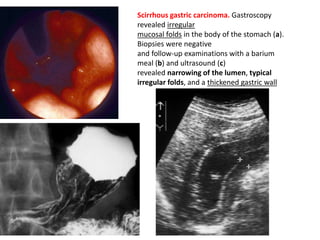

• Radiographically this usually appears as a

narrowed, rigid stomach.

scirrhous carcinoma with linitis plastica

appearance.

Poor distensibility of the stomach is shown

on the barium study (a) and wall thickening

confirmed by CT